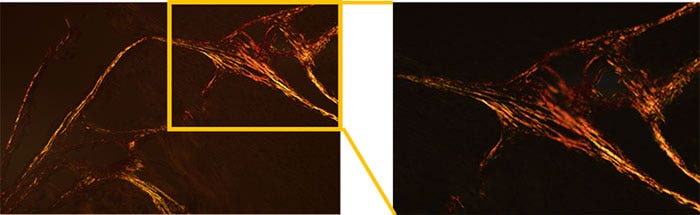

Figure 3: Sample image*

Figure 4: Measurement results

*Red shows collagen type Ⅰ, Green shows collagen type III